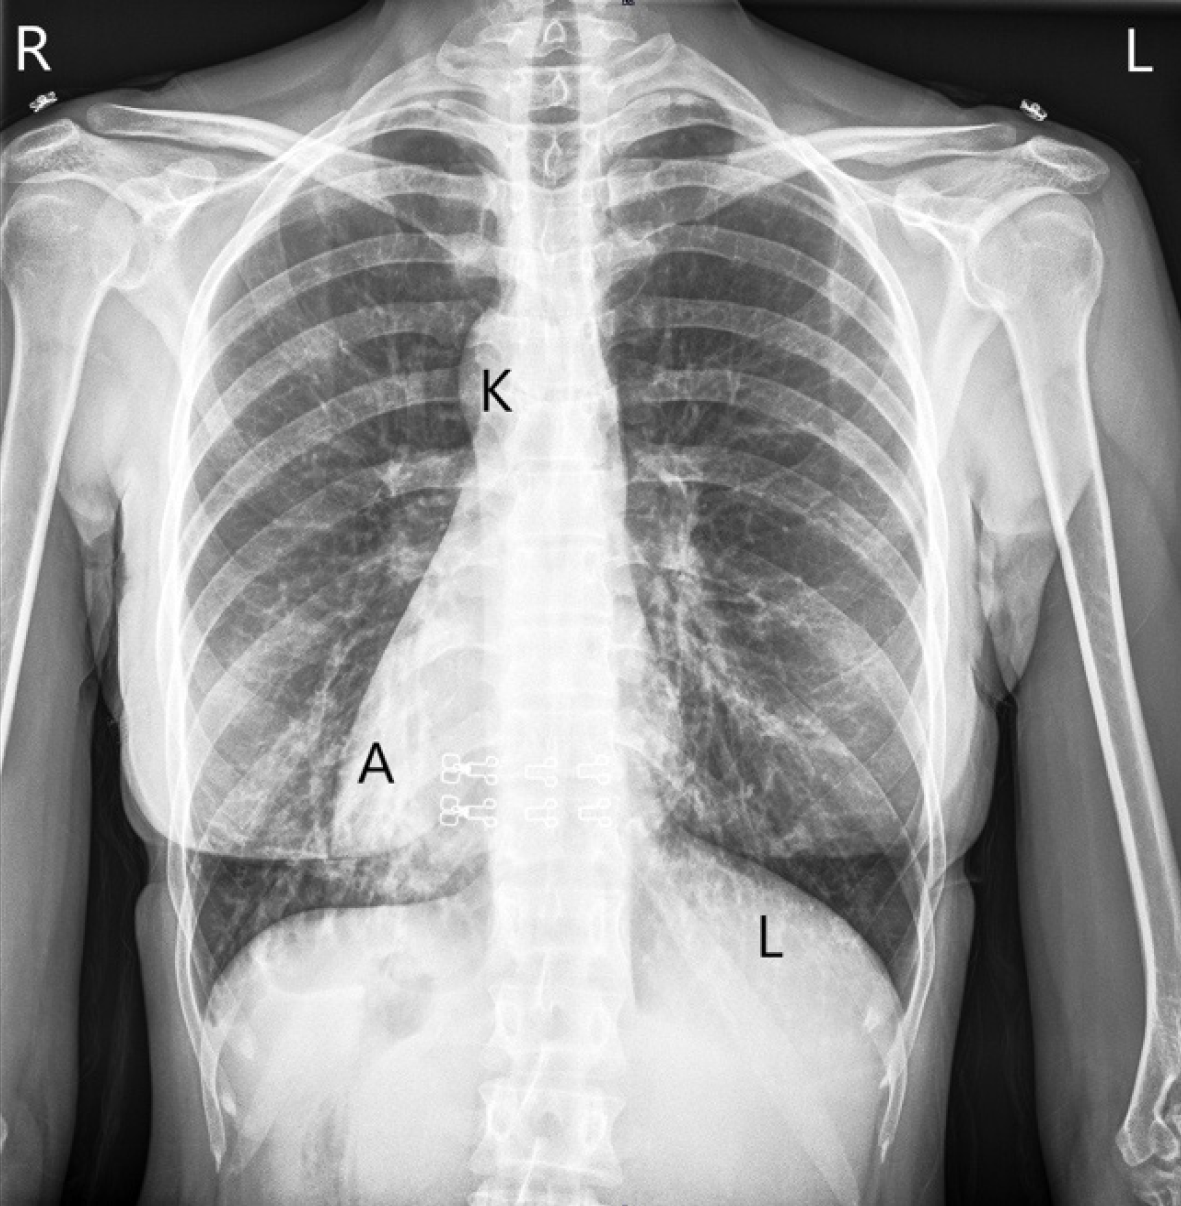

Case 1: Laboratory investigations revealed anemia with mild biochemical abnormalities; viral markers were negative (Table 1 and Figure 1).

Case 1: Chest radiography demonstrated dextrocardia. Abdominal ultrasonography and magnetic resonance cholangiopancreatography confirmed cholelithiasis and SIT (Figure 2).